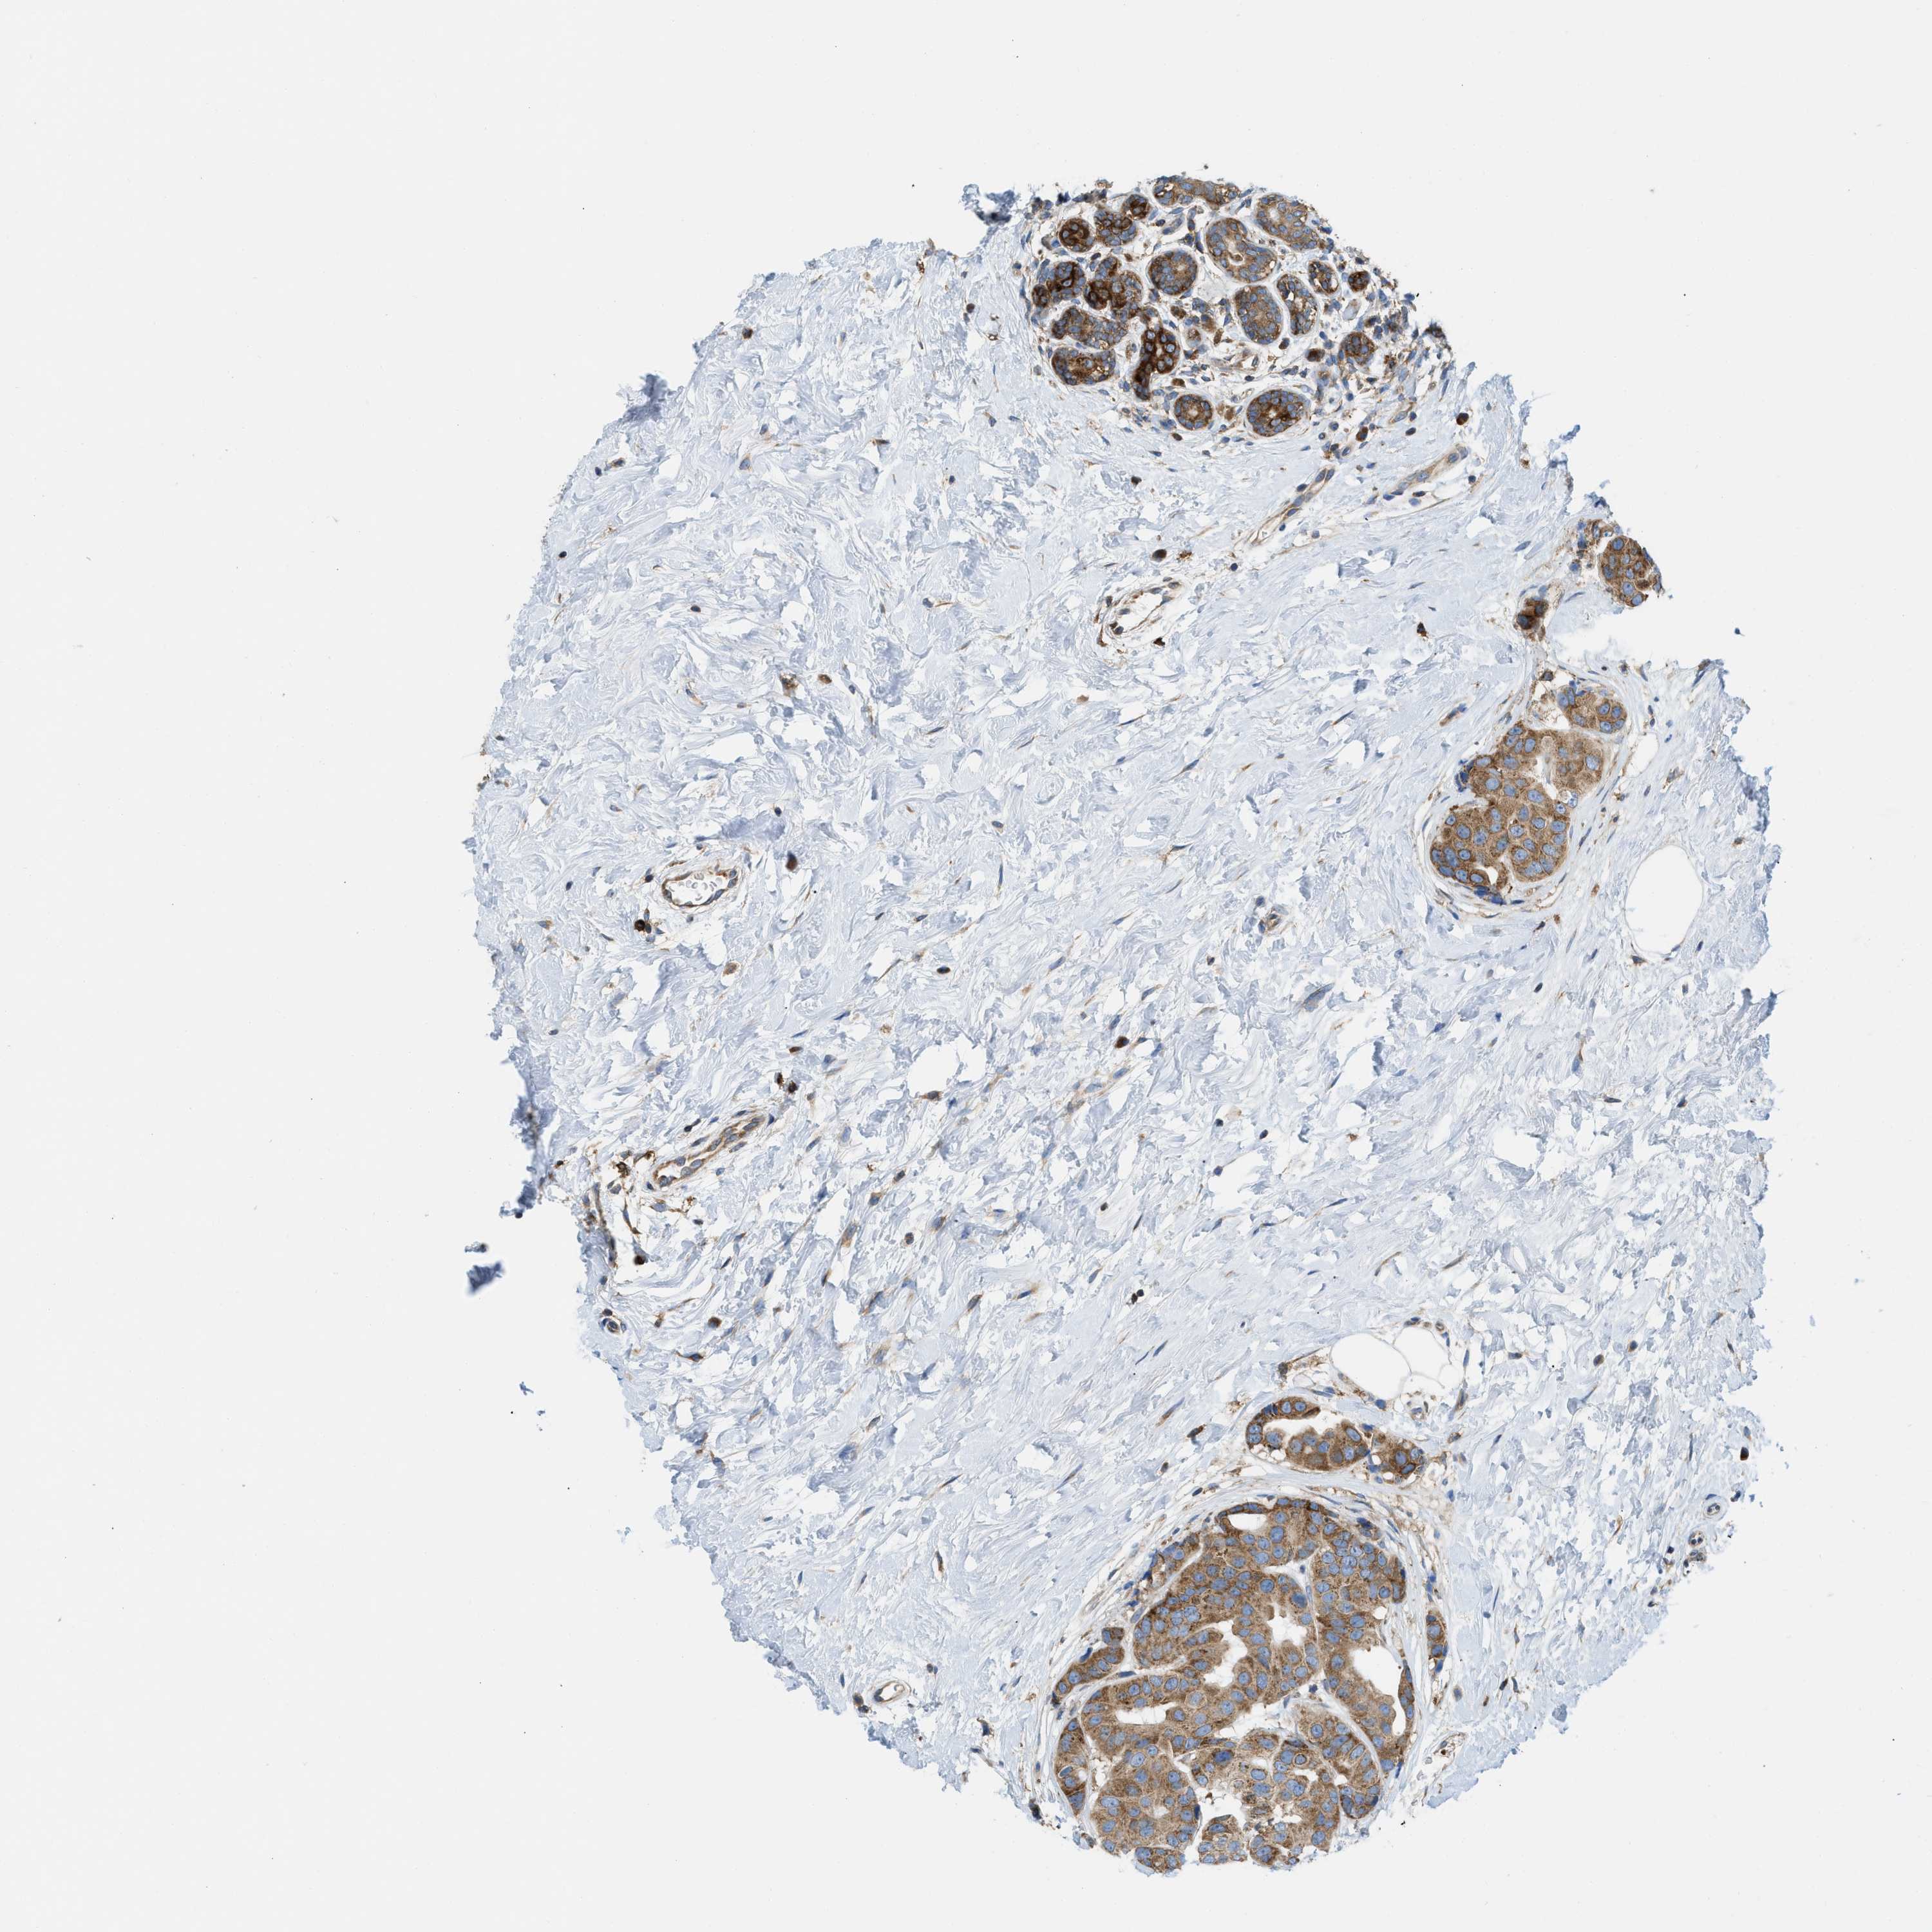

CANCER BREAST CANCER Show tissue menu

BRCA TCGA BRCA VALIDATION PROTEIN EXPRESSION